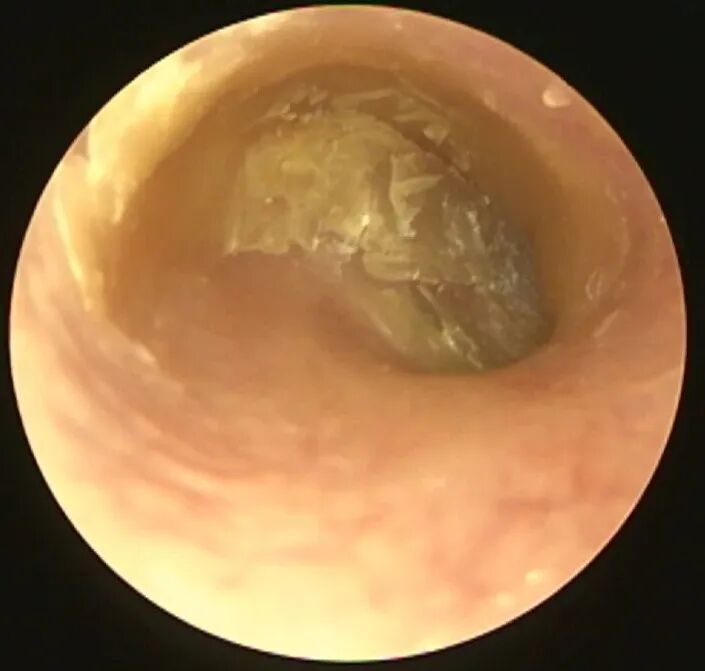

耳内镜下的操作需要细心、耐心和手巧,需要观察并清理外耳道每一个角落,比如

乍一看,已经比较干净了哦,但是如果换个角度就会发现

在边缘的角落里还有一些痂皮没有清理干净,这往往是复发的隐患,一定要彻底清理。